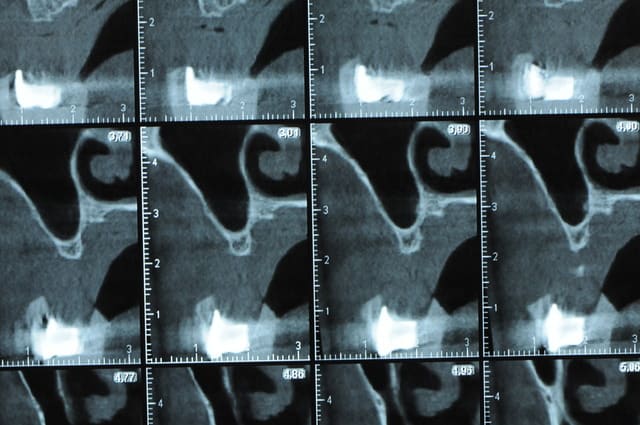

Une petite étude de ton cas D57

Sous réserves bien sur de voir l’animal en vrai

Les zones exploitables radiologiquement parlant:

Coupes implant

2,3 40100

4,96 35130 avec sinus lift mais difficile

5,25 35150

6,02 35130

6,78 35115 après réduction de hauteur de crête

7,26 35115 après réduction de hauteur de crête

8,51 35150

10,43 40115 ou 50115

11,10 40115

Ce qui nous fait 9 implants possible évidement avec un comblement de sinus on augmenterait encore les zones implantable mais ce n’est pas le but recherché, avec 8 (4+4) il doit être possible de faire une belle barre support de complet